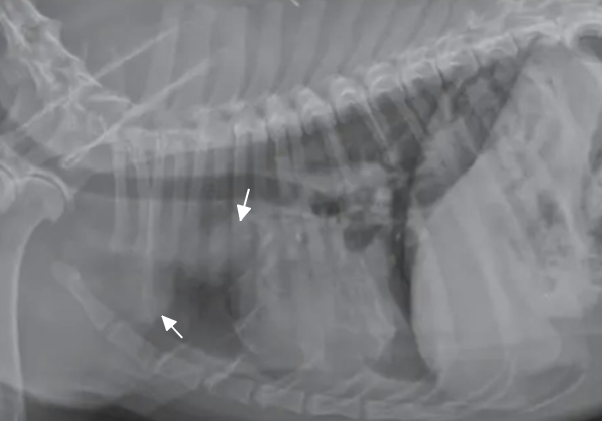

![]() | sternal lymph node 폐결절이면 이렇게 벽에 딱 붙어있진 않을 것 |

![]() | mast cell tumor가 화살표 쪽에 전이됨. (cranial mediastinal lymphadenopathy) |

![]() | - Cranial mediastinal(위쪽) - Sternal (아래쪽) |